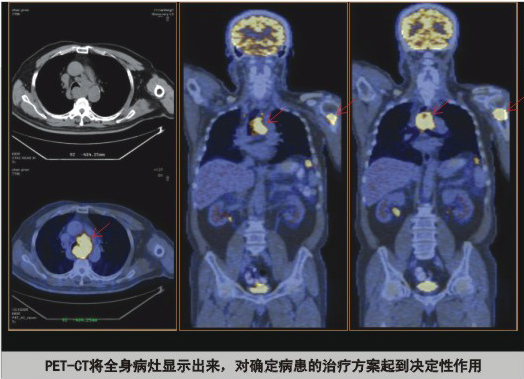

3、 治療方案的制定

對于腫瘤來說,CT、MR檢查局限性較大,而PET-CT檢查通過一次全身掃描就可以發(fā)現(xiàn)惡性腫瘤是否已經(jīng)擴(kuò)散,這樣可以給患者制定一套合理的治療方案,避免了因不必要的手術(shù)給患者帶來的痛苦和經(jīng)濟(jì)損失,從PET-CT投入臨床應(yīng)用以來的數(shù)據(jù)統(tǒng)計(jì)約有40%的患者通過PET-CT檢查后改變了治療方案。

PET-CT將全身病灶顯示出來,對確定病患的治療方案起到?jīng)Q定性作用。